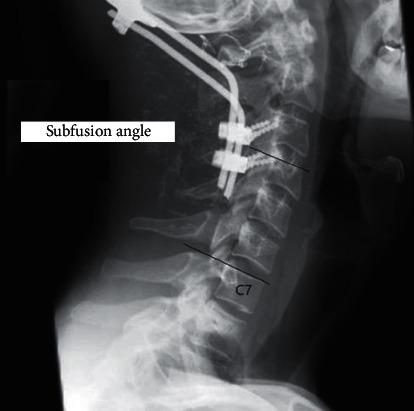

The primary outcome measure is the evaluation of sagittal cervical alignment roentgenographic parameters and the secondary is the functional outcome (NDI), following POCF for upper (C1 & C2) cervical trauma (UCT) in coexistence with upper cervical spine degeneration. . Twenty old and elderly patients aged 62 ± 12 years with evident upper cervical degeneration, who received POCF for upper C1 & C2 unstable cervical spine injuries, were included. C2-C7 lordosis, C2-C7 SVA, spinocranial angle (SCA), T1-slope, neck tilt (NT), thorax inlet angle (TIA), cervical tilt (CT), cranial tilt (CrT), and C0-C1 angle were measured. The subfusion angle was used to study the behavior of the unfused cervical segments below fusion. The Neck Disability Index (NDI) was used for the functional outcome evaluation. 29 age-matched individuals were used as controls for radiographic analysis and self-reported functional status comparison.

The roentgenographic data were measured 3 and 39 ± 12 months postoperatively. Twelve patients showed no disability, and eight showed mild disability. Postoperatively, the patients stood with less C2-C7 lordosis, SCA, and CT ( < 0.02) but with higher NT ( < 0.02) in comparison to the controls. The patient's neck disability (NDI) was increasing as TIA increases (=0.023). Subfusion angle seems to adapt to C2-C7 lordosis ( < 0.0033) and C0-C2 angle ( < 0.003) without any changes till the last evaluation.

主要观察指标是评估POCF治疗合并上颈椎退变的上颈椎(C1和C2)创伤(UCT)后颈椎矢状位对线的影像学参数,次要观察指标是功能结局(NDI)。纳入20例年龄在62±12岁、存在明显上颈椎退变、因C1和C2颈椎不稳损伤接受POCF治疗的老年患者。测量C2-C7前凸、C2-C7矢状面垂直轴(SVA)、脊柱-颅骨角(SCA)、T1斜率、颈部倾斜度(NT)、胸廓入口角(TIA)、颈椎倾斜度(CT)、颅骨倾斜度(CrT)和C0-C1角。用融合下角度研究融合下方未融合颈椎节段的情况。采用颈部功能障碍指数(NDI)评估功能结局。选取29例年龄匹配个体作为影像学分析和自我报告功能状态比较的对照。

术后3个月及39±12个月测量影像学数据。12例患者无功能障碍,8例有轻度功能障碍。术后与对照组相比,患者站立时C2-C7前凸、SCA和CT减小(P<0.02),但NT增大(P<0.02)。患者的颈部功能障碍(NDI)随TIA增加而增加(P=⁠0.023)。融合下角度似乎适应C2-C7前凸(P<0.0033)和C0-C2角(P<0.003),直至最后一次评估均无变化。